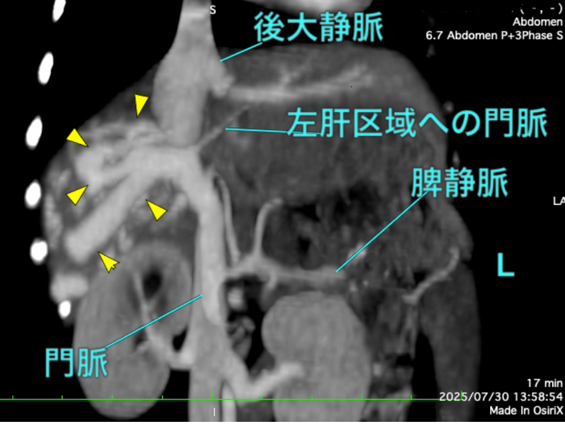

肝内門脈シャントの精査を目的にCT検査を実施しました。検査の結果、右外側肝葉において肝内門脈から体循環へのシャントが確認され、後大静脈へ流入する血管が約5本(うち1本は太く、残りの4本は細い)存在することが判明しました。 また、右外側肝葉への血流が非常に豊富である一方、他の肝葉への門脈血流は細いことが確認されました。そのため、右外側肝葉切除を行った場合には術後に門脈圧亢進を生じる可能性が高いと判断されました。 これらの所見を踏まえ、段階的な肝内門脈シャント閉鎖を目的とした血管プラグ塞栓術を希望され、施術する運びとなりました。

手術前のCT検査での評価